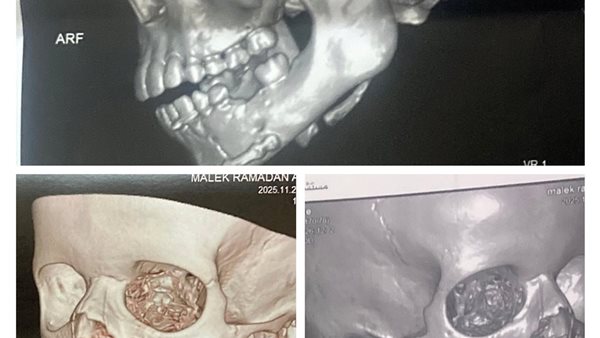

وأضافت وكيل وزارة الصحة والسكان بمحافظة الفيوم، أن الطفل "م ر ع" 9 سنوات، دخل قسم الاستقبال في مستشفى الفيوم العام، مصابا بكسر في زاوية الفك السفلي بالجهة اليمنى وكسر بمقدمة الفك، بعد تعرضه لحادث سير.

وتم تحضير المريض للعملية بعد استقرار الحالة والاطمئنان على العلامات الحيوية، وتمكن فريق جراحة الوجه والفكين من رد وتثبيت الكسر بالشرائح والمسامير المعدنية تحت مخدر عام واستعادة الوظيفة الكاملة للفك السفلي مع الحفاظ على براعم الأسنان الدائمة، وبعد إفاقة المريض والاطمئنان على استقرار حالته، تم صرفه لاستكمال العلاج بالمنزل.